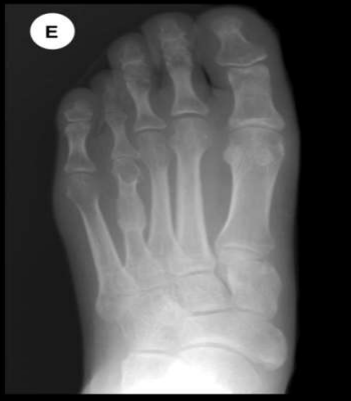

Fig: 1 The radiographs show an anteroposterior view of before and after operation of bone graft.

Figure 1